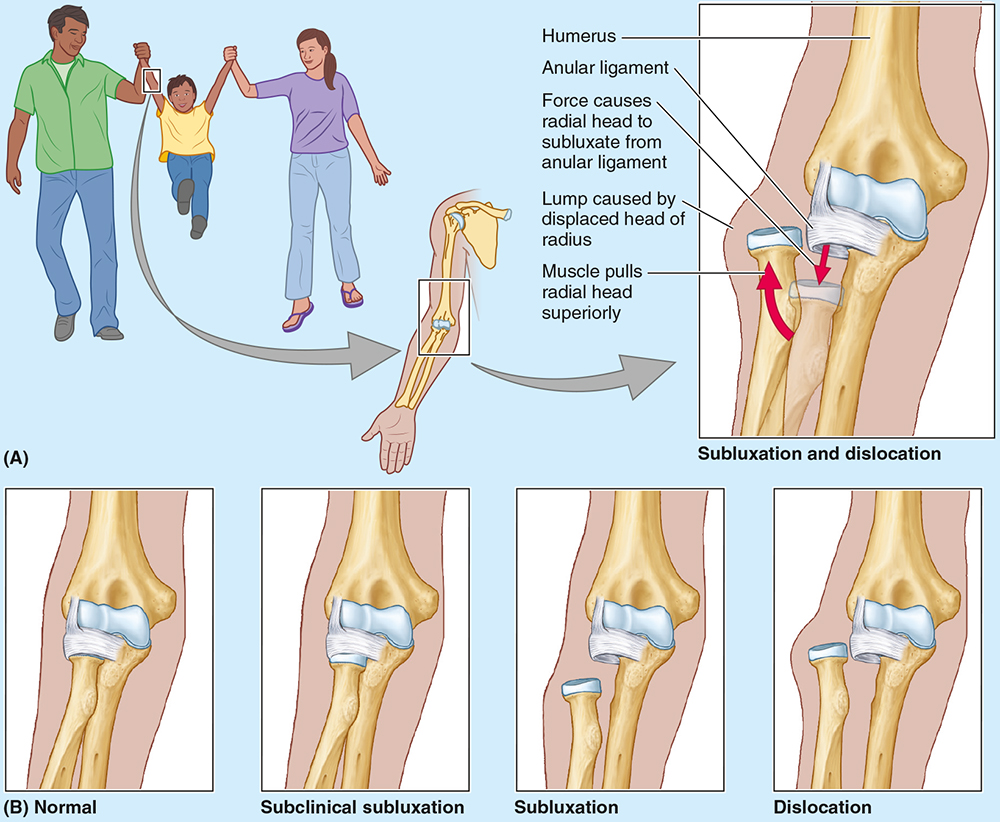

Nursemaid’s elbow is a common injury in preschool children, especially girls, caused by sudden pulling of the pronated forearm (e.g., lifting a child). The _________ tear causes subluxation of the radial head.

annular ligament

Nursemaid’s elbow is a common injury in preschool children, especially girls, caused by sudden pulling of the pronated forearm (e.g., lifting a child). The annular ligament tear causes __________ of the radial head.

subluxation

Treatment of nursemaid’s elbow involves?

Treatment involves supination with elbow flexion; healing occurs with sling use for 2 weeks.

The elbow is stabilized by the ulnar and radial collateral ligaments, whereas the _____________ holds the radius against the ulna for rotation.